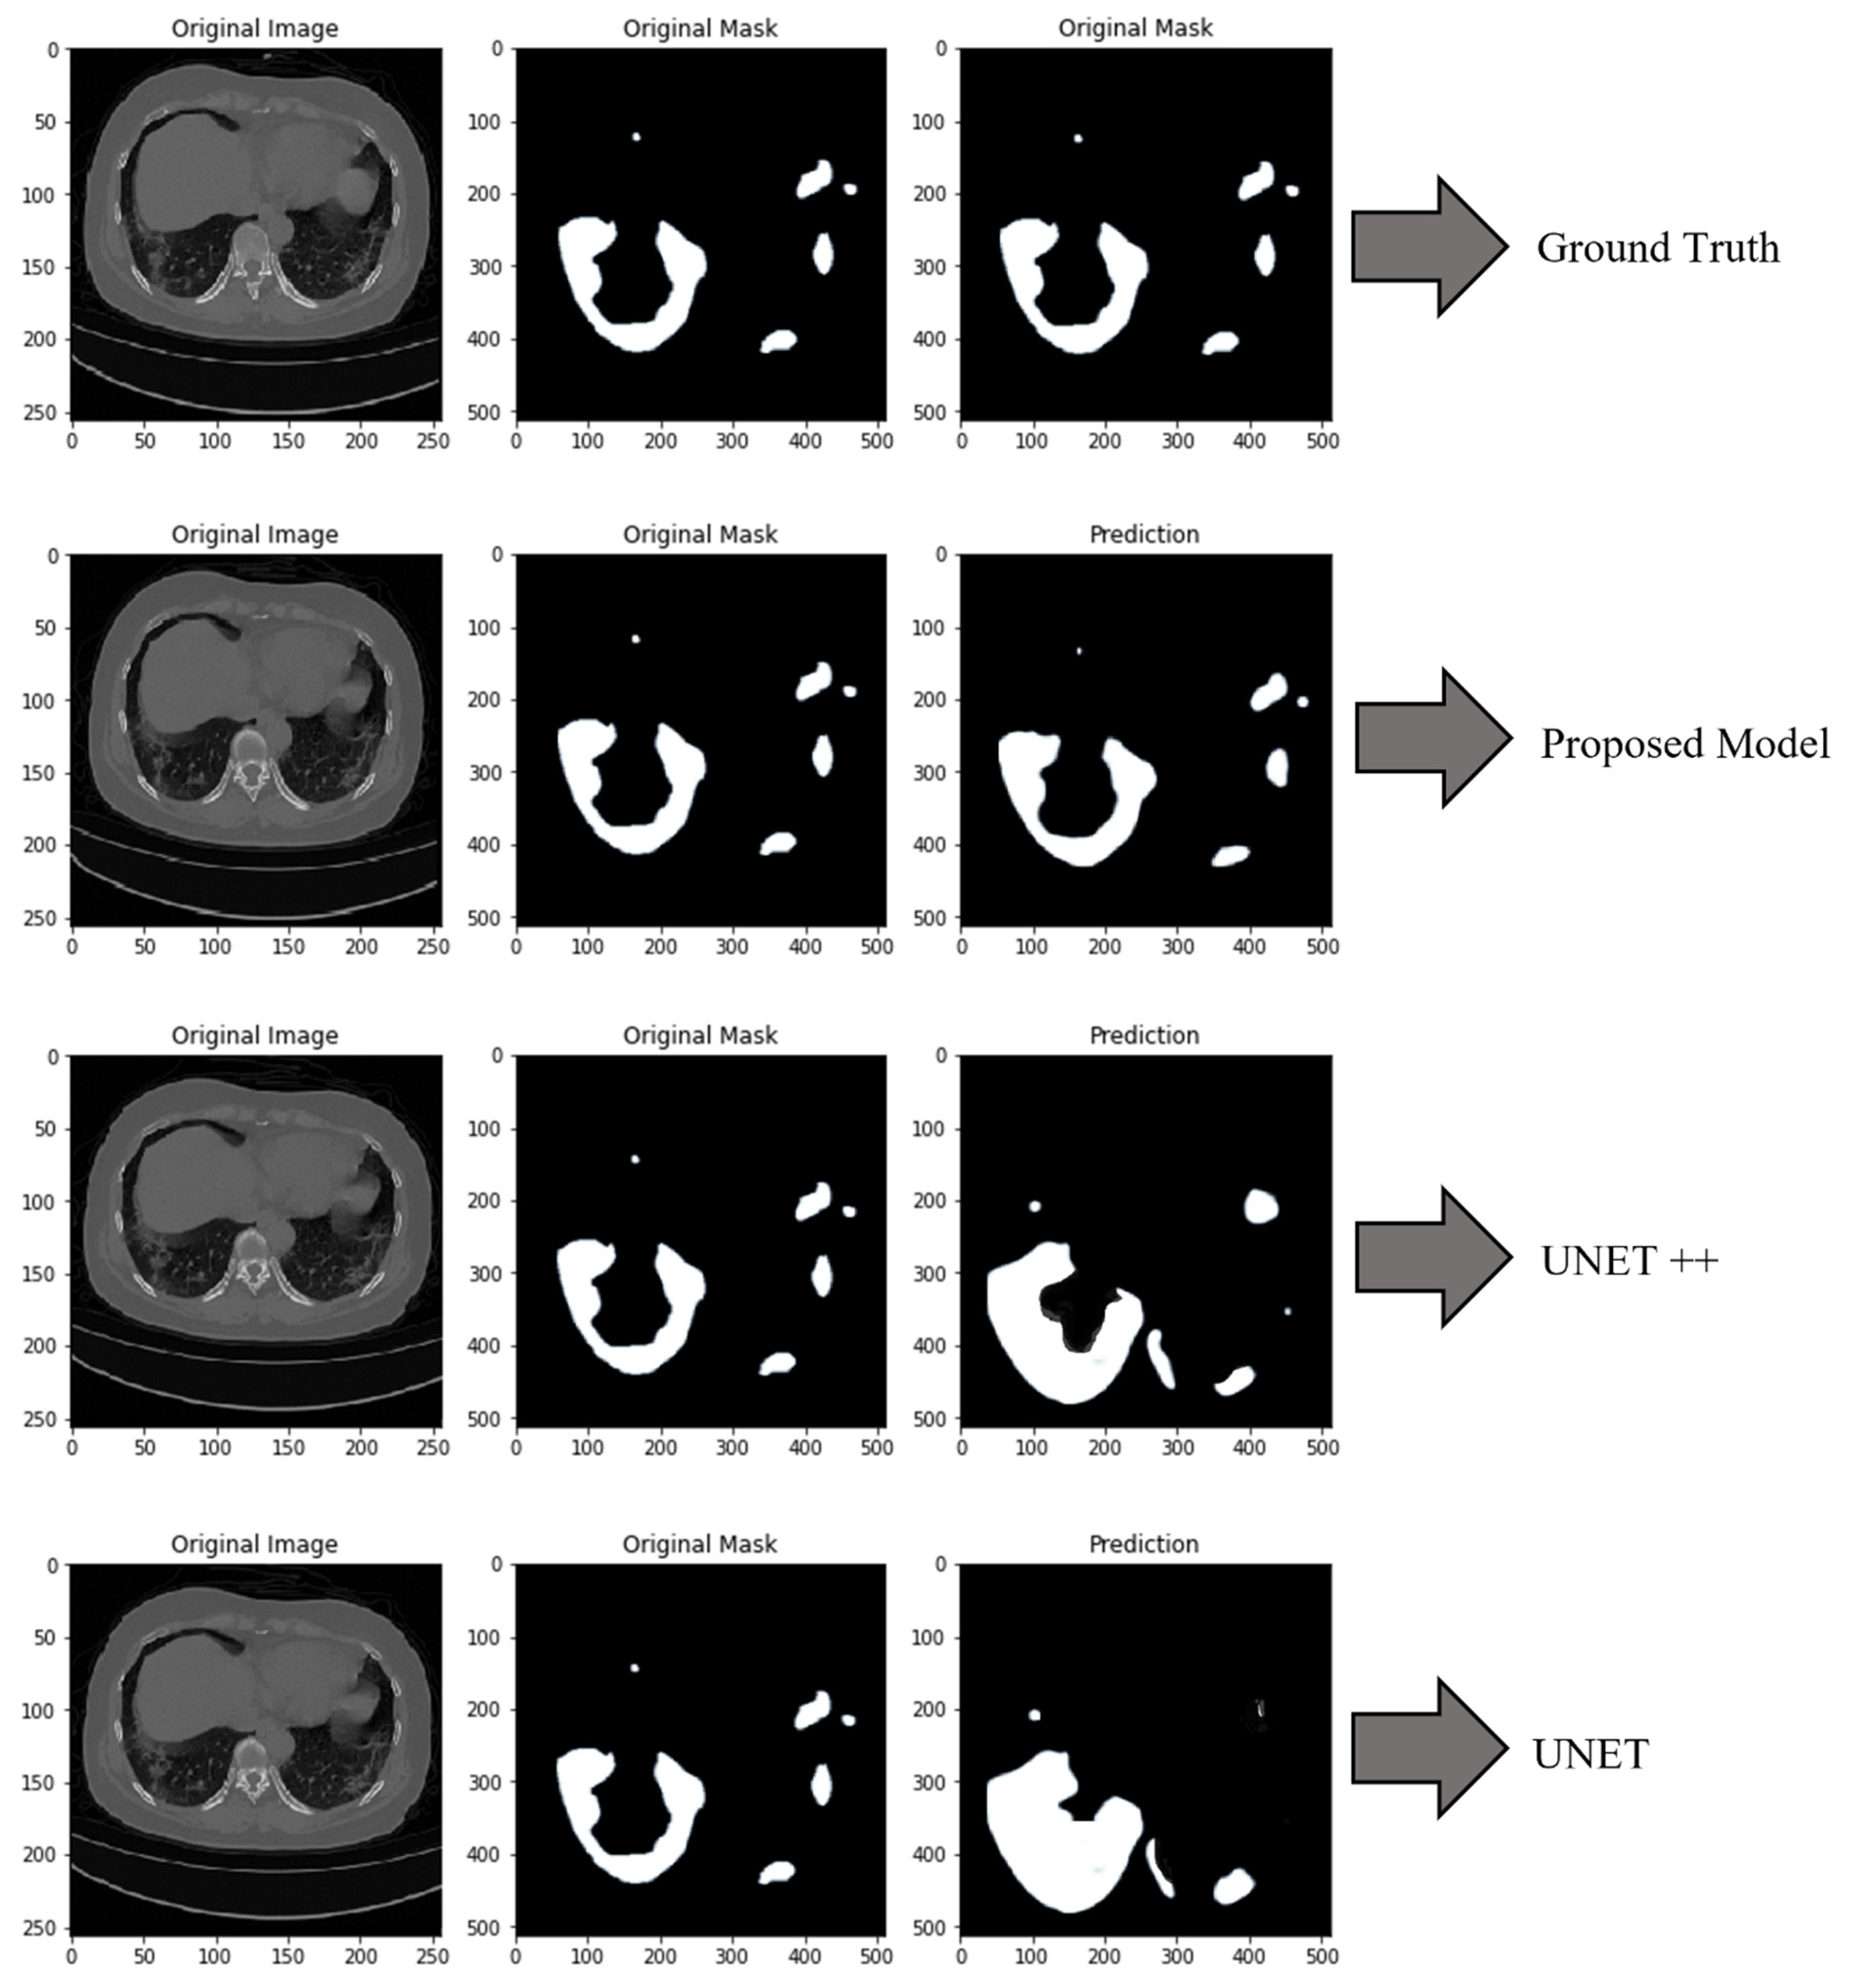

| Models | ACU | PRE | REC | SPF | F1-Score | DSC |

|---|---|---|---|---|---|---|

| UNET | 84.15% | 84.42% | 84.99% | 84.75% | 84.22% | 84.19% |

| UNET++ | 86.10% | 86.99% | 86.09% | 86.99% | 86.02% | 86.01% |

| Proposed Model | 95.81% | 95.49% | 95.32% | 95.57% | 95.51% | 95.50% |